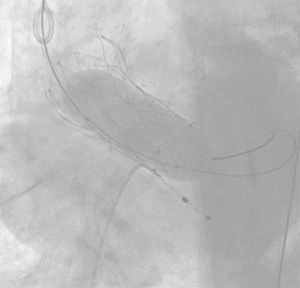

Existen numerosos escenarios que motivan el planteamiento de la post-dilatación tras el implante de una TAVI. Quizá el más importante (por su elevada frecuencia y repercusión negativa) sea la reducción de la severidad de una RPV, pues el baloneo promueve una expansión óptima de la prótesis (figs. 3 y 4). Con ello, también se consiguen un aumento del área valvular efectiva, una disminución de los gradientes y, en consecuencia, una reducción del mismatch (que se ha asociado a una mayor incidencia de trombosis valvular clínica y subclínica)46.

Post-dilataciónAtendiendo a los resultados angio y ecocardiográficos, así como a los parámetros anteriormente referidos, valoraremos la necesidad de añadir la post-dilatación al procedimiento.

La situación que más frecuentemente plantea la necesidad de post-dilatar es la existencia de una RPV (fig. 6). Quizá la envergadura de la misma (moderada/severa) sea uno de los factores más potentes, pero debemos atender también a otras características. Un paciente joven, de moderado/bajo riesgo, con anatomía favorable y sin comorbilidad o trastorno previo de la conducción se beneficiaría, sin duda, de la misma. También el implante de prótesis autoexpandibles, estenosis aórtica pura previa o aquellos casos en los que prima una gran durabilidad del implante.

Contrariamente, la mencionada post-dilatación puede conllevar más riesgos que beneficios en pacientes ancianos, de alto riesgo y comórbidos (trastornos de la conducción, ictus), con amenaza de rotura anular o embolización del dispositivo al añadir manipulaciones. Si durante la RPV es ligera, la anatomía hostil y en el preoperatorio presentaban doble lesión aórtica, parece también prudente obviar este paso.